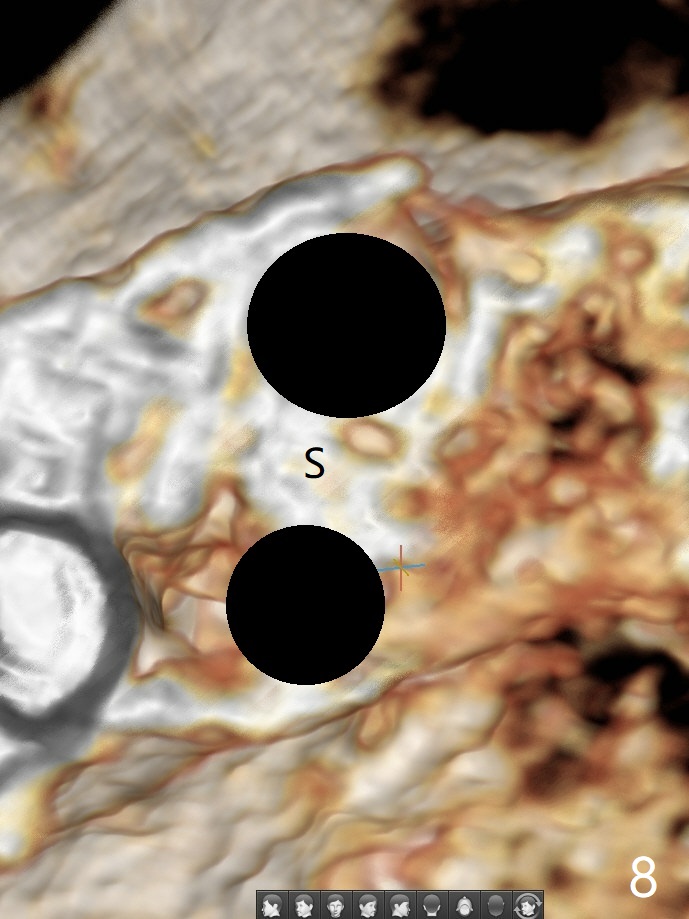

52岁女左上4颊侧牙龈显著肿胀(图一:*(颊侧骨板缺失))伴有瘘道(<),拔除前,在3植牙牙冠切缘舌侧形成开口(图二:*,准备纠正基台不全就位(<);4初步钻洞不正。改变钻头方向后(图三),完成植体放置(图四),并且安置修复基台(4.5x4(2))。磨去3牙冠近中面(图六:*),牙冠和基台反时针旋转(图六:弯箭头),基台完全就位(图四:箭头),调𬌗后,制作4临时牙冠(图六),放置后者前,覆盖半张PRF膜(促进下面粘性骨粉愈合)。图五,六颊侧隆起是因为下面放置许多粘性骨粉。图七是术前CT3D图像(冠状切面),显示颊侧(B),腭侧(P)牙根。拔牙后显示中隔(图八:S),植体植入腭侧窝(图九:绿色),四面骨质包绕,包括中隔;为了修复颊侧骨板,首先放置半张PRF膜(红色)紧贴颊侧骨板腭侧/牙龈,防止骨粉从瘘道流失,然后放置粘性骨粉(图十:粉红色)。术后2.5月3颊侧牙龈仍然红肿(图十一,十二:*),可能与基台袖太短有关(2毫米,图二至四),所以更换袖3毫米的基台(图十三)。术后四个月(牙冠粘固)3颊侧牙龈炎症明显减退(资料没有显示)。术后2.5月4颊侧骨板没有塌陷(图十二,与术后即刻对比(图六))。3基台放置太颊侧,所以在牙冠腭侧制作小的开口(图十四:>),让多余粘固剂流出。取模前3螺丝就拧紧(35Ncm),而4由于有大的开口,粘固后才拧紧(30Ncm)。两个邻牙其中一个可以取出,容易去除另外一个牙冠残余粘固剂。